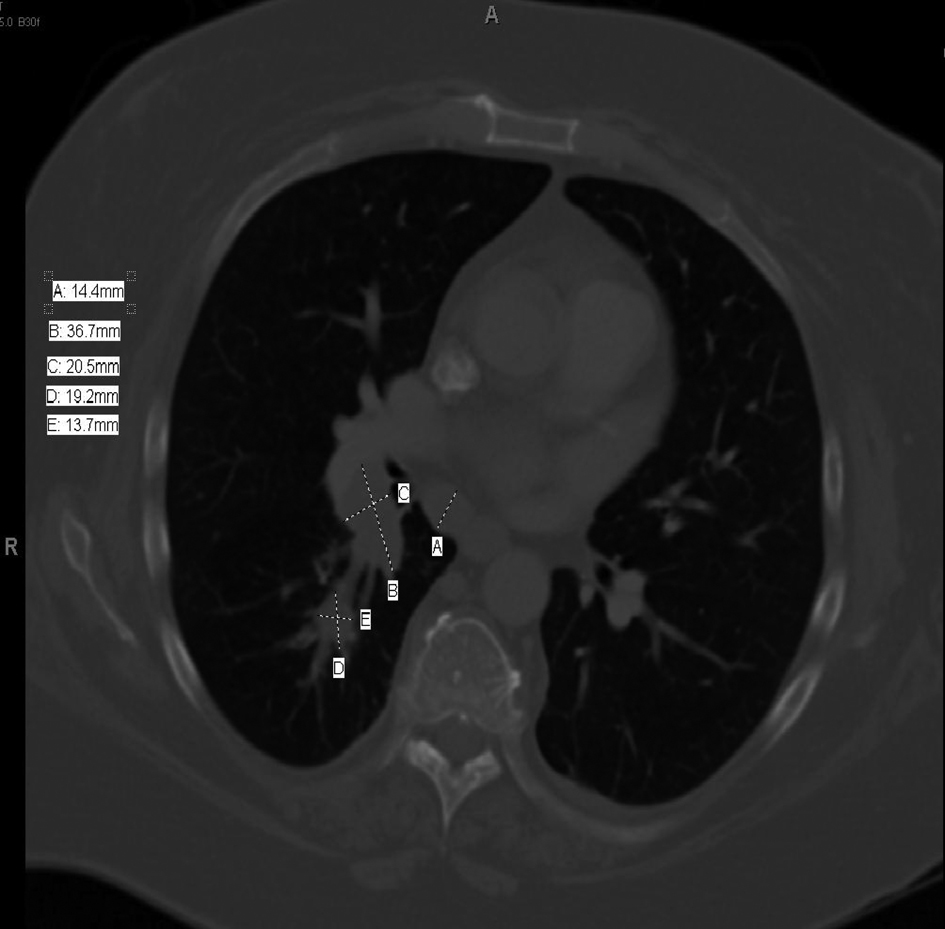

CT Chest (Fig. 1) showed a 3.7 cm right hilar mass, bronchoscopic biopsy (Fig. 2) showed small cell lung carcinoma (SCLC). Staging work up ruled out brain, liver or adrenal lesions. Her bone scan was negative for metastases.

![]() Click for large image | Figure 1. CT chest. |